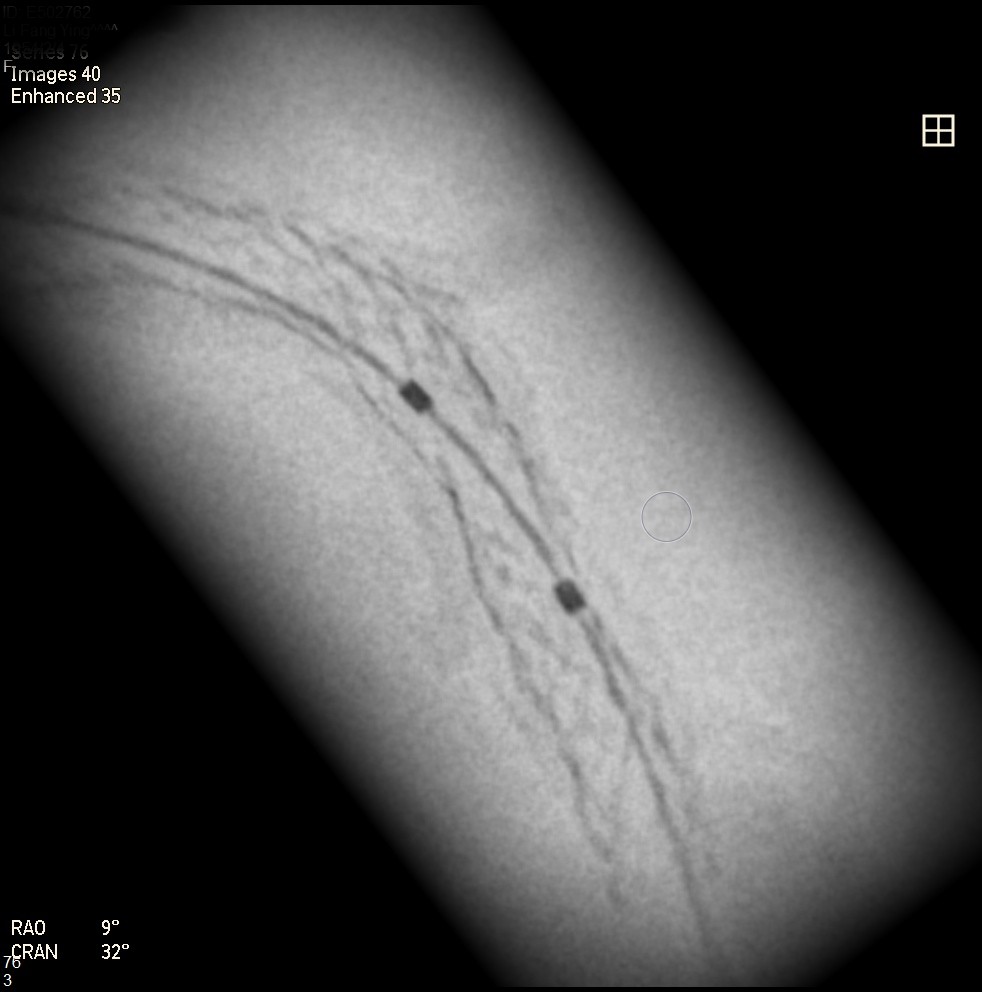

Initially, we tried to insert IVUS catheter but unable to cross the lesion. We tried a NC balloon but unable to cross it also.Hence, we used rotational atherectomy with 1.5mm burr. However, the burr was unable to cross lesion even in high speed and entrapped in the stent.We removed the burr in guide extension catheter then the NC balloon could cross the lesion. The IVUS cather could also cross it with guide extension catheter support. The stent was almost not expanded. We tried NC balloon high pressure dilation but balloon slippage and burst. The lesion was still un-dilatable. We insert cutting balloon which avoided slippage but remained burst. We escalated the burr size to 1.75mm. The larger burr was not stucked but still unable to cross lesion. Besides, the larger burr causing slow blood flow. After adenosine injection, the patient's blood flow recovered. We reduced the burred size to 1.25mm which cross the lesion once but entrapped while doing polishment. After burr retrieval, we used NC balloon high pressure dilation. The balloon bursted but the lesion remained un-dilatable.Finally, the lithotrypsy balloon could cross the lesion and eliminate 80 pulses. The lesion was expanded much well. The IVUS showed the old stent was expanded and calcium was cracked. We deployed a new stent for old one destruction and proximal dissection. The final IVUS image showed epansion and apposition were accpetable.